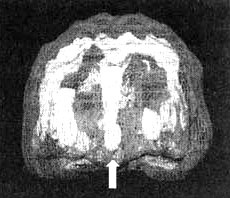

Мозг Гейл. Обсессивно-компульсивное расстройство (ОКР)

Иллюстрация к книге — Измените свой мозг - изменится и жизнь! [i_060.jpg]

Трехмерное изображение — активный мозг, вид спереди. Обратите внимание на значительное усиление активности в поясной системе (см. стрелку).

Будучи уже на грани развода, Гейл с мужем пришли ко мне. Поначалу к мысли о том, что природа заболевания Гейл имеет биологический характер, ее муж отнесся крайне скептически. Однако сканирование SPECT выявило у нее значительно повышенную активность в поясной системе, из чего следовало, что ей на самом деле было сложно переключать внимание.

В последние годы было проведено любопытное исследование, в ходе которого была установлена биологическая природа ОКР. Сканирование SPECT выявило избыточное кровоснабжение поясной системы в сочетании с повышенной активностью базальных ганглиев (нередко ответственных за тревожность, отмечающуюся у этих больных).